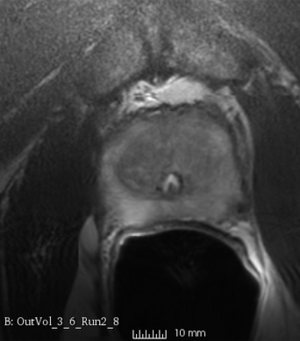

Case 7

Reference intraop volume

Reg Result Slicer 3.6 with ITKv3

Reg Result Slicer 4.4 with ITKv4